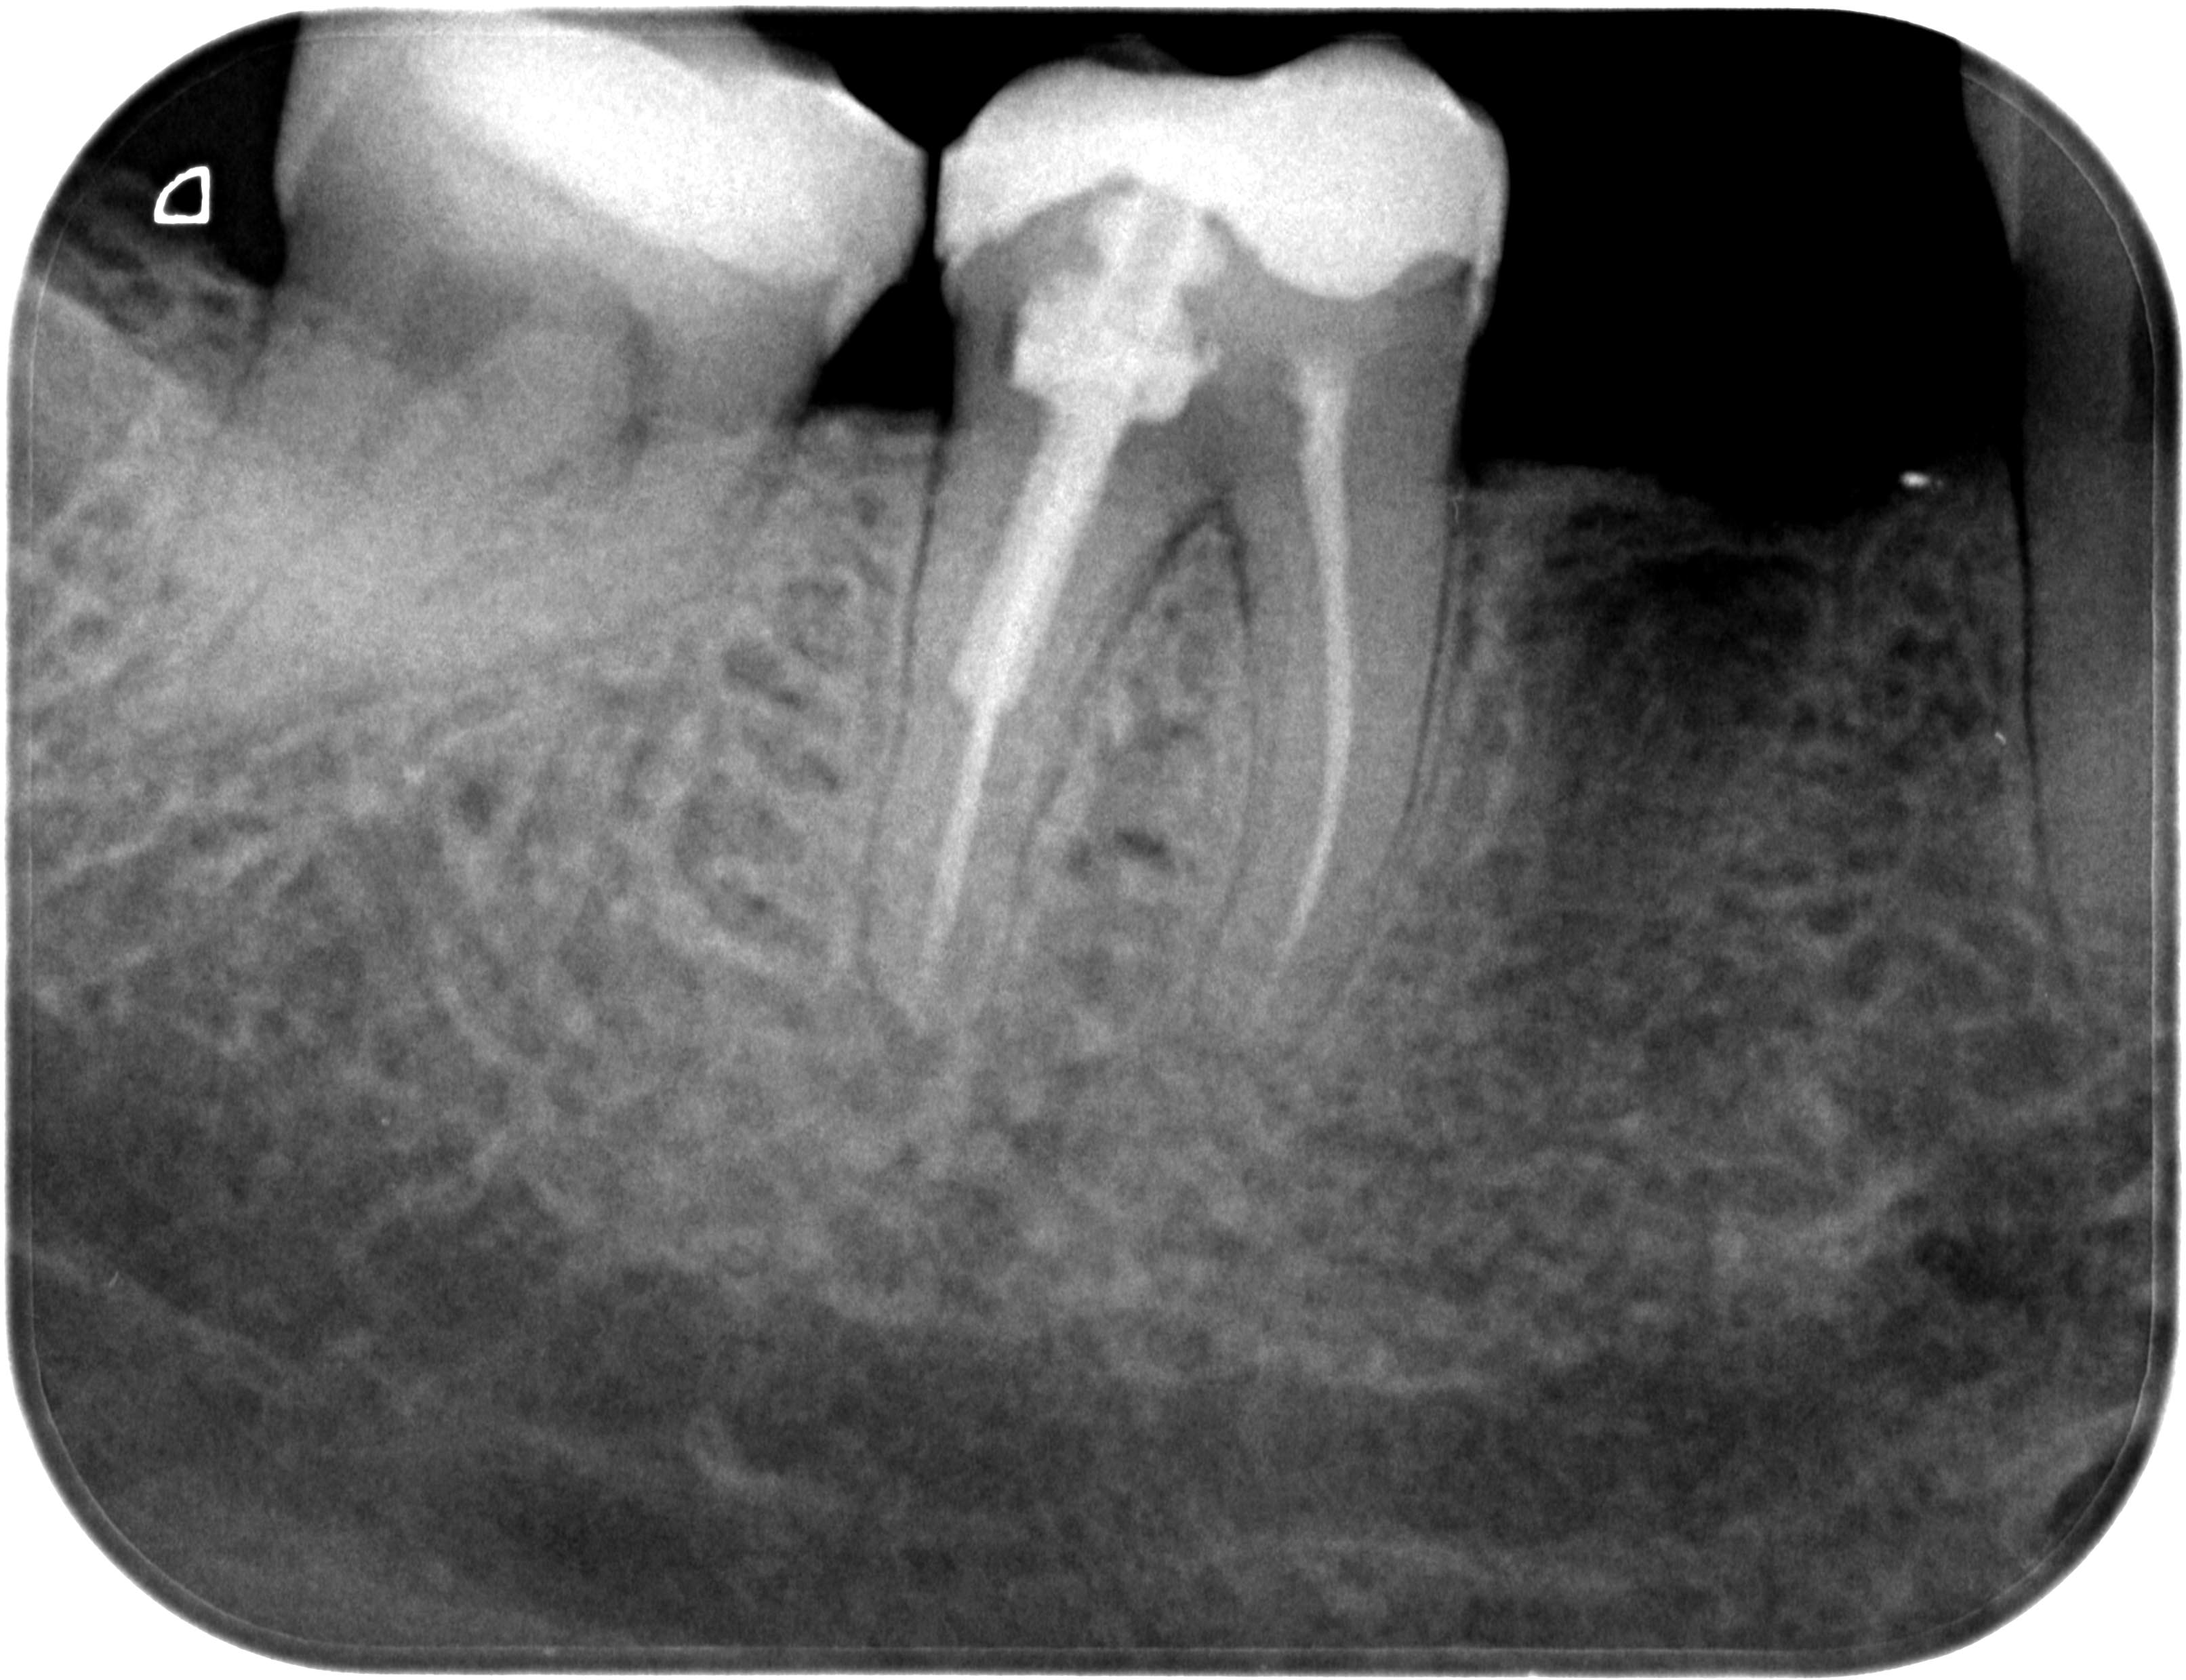

Resorption-1-2 Veröffentlicht 10. Juni 2013 am 3225 × 2479 in Was zeigt das DVT (4) ? Die Fälle Zahn 47, 46